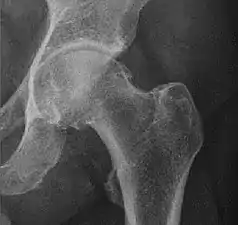

Adults

Landmarks

In the adult hip there are important landmarks to be recognized on plain film radiographs:[3]

- The iliopectineal or iliopubic line is formed by the arcuate line of the ilium and the superior border of the superior pubic ramus up to the pubic symphysis. It conforms to the inner margin of the pelvic ring and it is part of the anterior column of the acetabulum.

- The ilioischial line of Köhler begins at the medial border of the iliac wing and extends along the medial border of the ischium to end at the ischial tuberosity. It is part of the posterior column of the acetabulum.

- The acetabular floor.

- The teardrop represents a summation of shadows. Its medial aspect corresponds to the inner cortex of the pelvis and the lateral edge with the acetabular notch and the anteroinferior portion of the quadrilateral plate. It is not present at birth but gradually develops due to pressure of the femoral head.

Measurements

- Fossa/ilioischial relationship: In normal conditions the floor of the acetabular fossa is lateral to the ilioischial line by 2 mm in men and 1 mm in women. When the acetabular floor overlaps or overpasses the ilioischial line, the diagnosis of coxa profunda can be made. Nevertheless, coxa profunda had been found in 76% of asymptomatic hips, mainly in women. Therefore, this as an isolate criterion is not enough to make the diagnosis of pincer-type impingement. A more severe condition is protrusio acetabuli, diagnosed when the femoral head overlaps or overpasses the ilioischial line.[3]

- Joint space: In the adult hip, normal joint space ranges from 3 to 5 mm and must be uniform. Values under 2 mm are consistent with joint space narrowing.[3]